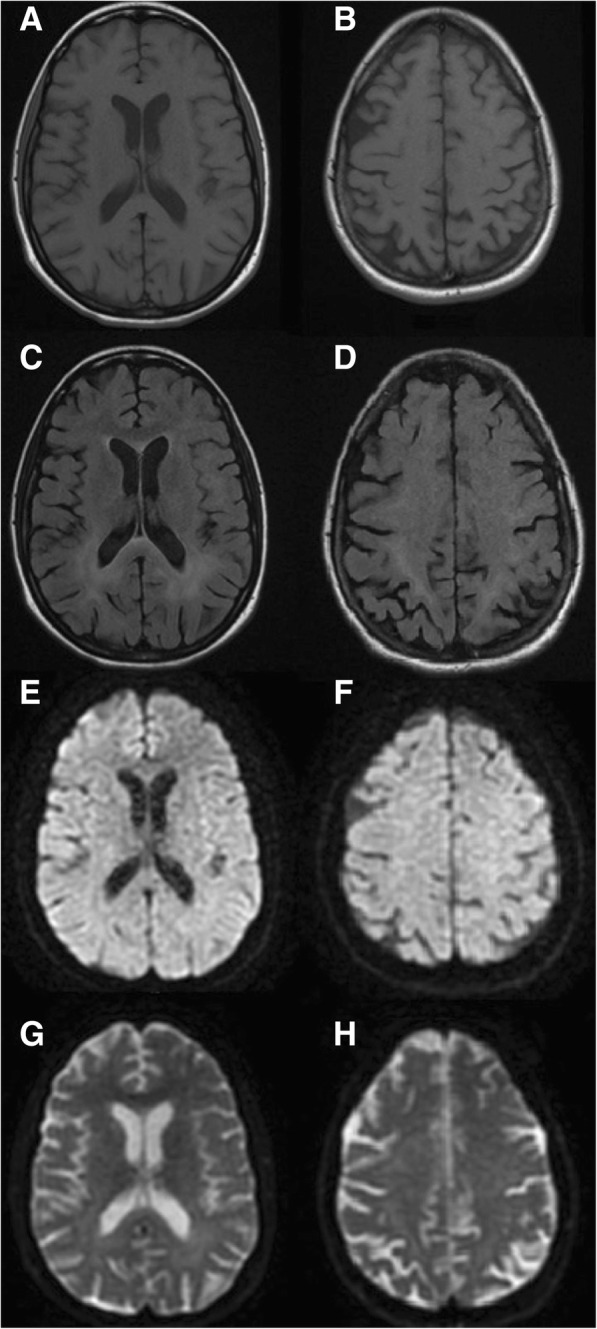

Brain MRI (Fig. 1) was consistent with HIV encephalopathy and electromyography (EMG) with the diagnosis of MNM (severe confluent multifocal demyelination and axonal loss in both upper and lower limbs).

Fig. 1.

Brain MRI. Axial T1 (a-b), T2/FLAIR (c-d), DWI (e-f) and ADC-map (g-h). Bilateral relatively symmetric periventricular and deep white matter T2/FLAIR hyperintensity predominantly in the posterior supratentorial area. Areas of restricted diffusion were not observed

The diagnosis of CMV encephalitis can be particularly challenging. Patients often present with progressive altered mental status which may be difficult to distinguish from HIV encephalopathy [6, 8, 9]. In contrast to HIV encephalopathy, CMV encephalitis has a more rapid onset (mean onset of less than four weeks) and symptoms of delirium, confusion, apathy, and withdrawal are more frequent [6, 8]. Yet, other non-distinguishing neurological manifestations, such as forgetfulness, memory impairment, and psychomotor slowing, are also common [6]. A more distinct type of CMV encephalitis characterized by ventriculoencephalitis has also been described and presents with rapidly progressive confusion and lethargy [6, 8], with variably associated radiculopathy and cranial nerve deficits [8]. MRI may show multiple hypertense foci distributed widely in the brain or periventricular enhancement on T2-weighted images, although these findings are inconsistently present and largely non-specific [18, 19]. Conversely, HIV encephalopathy typically shows widespread hyperintense lesions on T2-weighted/FLAIR, localized bilaterally in the deep white matter [18], a picture that more closely resembled the MRI findings in our patient. Similarly to CMV neurological disease, HIV RNA detection in CSF correlates significantly (albeit weakly) with the presence of HIV encephalopathy in untreated patients, an association not seen in patients on ART [20, 21]. However, CNS opportunistic infections may also increase intrathecal HIV replication [22].